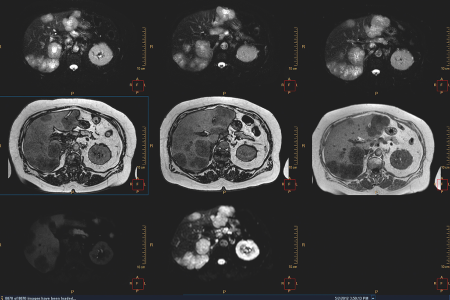

La cura del cancro si sta orientando verso scelte di trattamento ottimali e personalizzate, adattate in base alle esigenze dei singoli pazienti. Tutte le informazioni relative alla diagnostica e alla genomica del cancro vengono integrate per consentire agli specialisti del cancro di prendere decisioni informate durante la fase diagnostica. La digitalizzazione dell'assistenza sanitaria consente di rendere disponibili in formato digitale tutti i dati diagnostici, ad esempio i test radiologici, patologici e diagnostici in vitro.

In Philips, consentiamo la caratterizzazione e la stadiazione della malattia di un paziente in modo sicuro riducendo il rischio di errori nella categorizzazione della stadiazione.

Strumenti di visualizzazione avanzata oncologica che valutano lo stadio e la risposta al trattamento